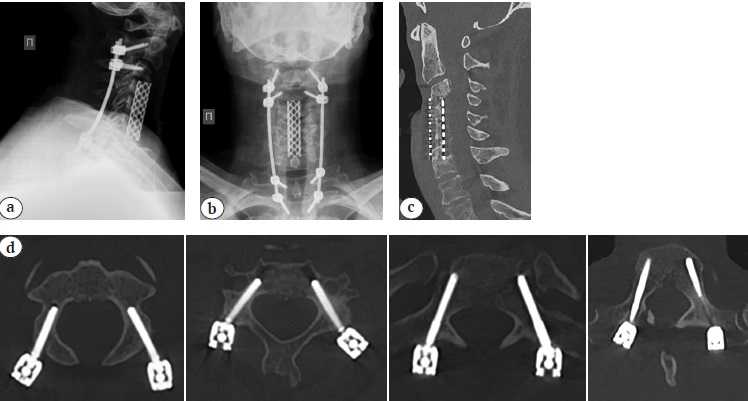

X-rays of the cervical spine at the time of discharge from the hospital and CT scans 10 months after the surgery are presented in Figure 5.

Fig. 5 (a, b, c, d). Sagittal (a) and frontal (b) X–rays, sagittal CT (c) 10 months after surgery: posterior transpedicular screw fixation correct position, solid anterior fusion C3–C7 formation detected. (d) - Axial (d) CT: posterior transpedicular screw fication correct position, solid anterior fusion C3–C7 formation detected

Postoperative period was uneventful, wounds healed by primary intention. Drains were removed on the 2nd day, patient was verticalized in a cervical brace on the 3rd day after the surgery. The intensity of vertebrogenic pain syndrome 10 months later was 2 points according to VAS, radicular pain syndrome in the upper extremities subsided, ODI – 15%, NDI – 14%. The value of correction of kyphotic deformity of the cervical spine was 46° according to Cobb.